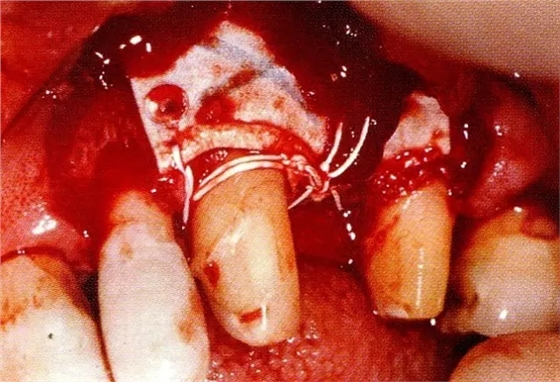

▲圖7-3將posterior interproximal類型的非吸收性覆膜修整后進行垂直懸吊縫合做固定。垂直懸吊縫合后,確定覆膜是否會動搖,再將齦瓣與之緊密縫合。